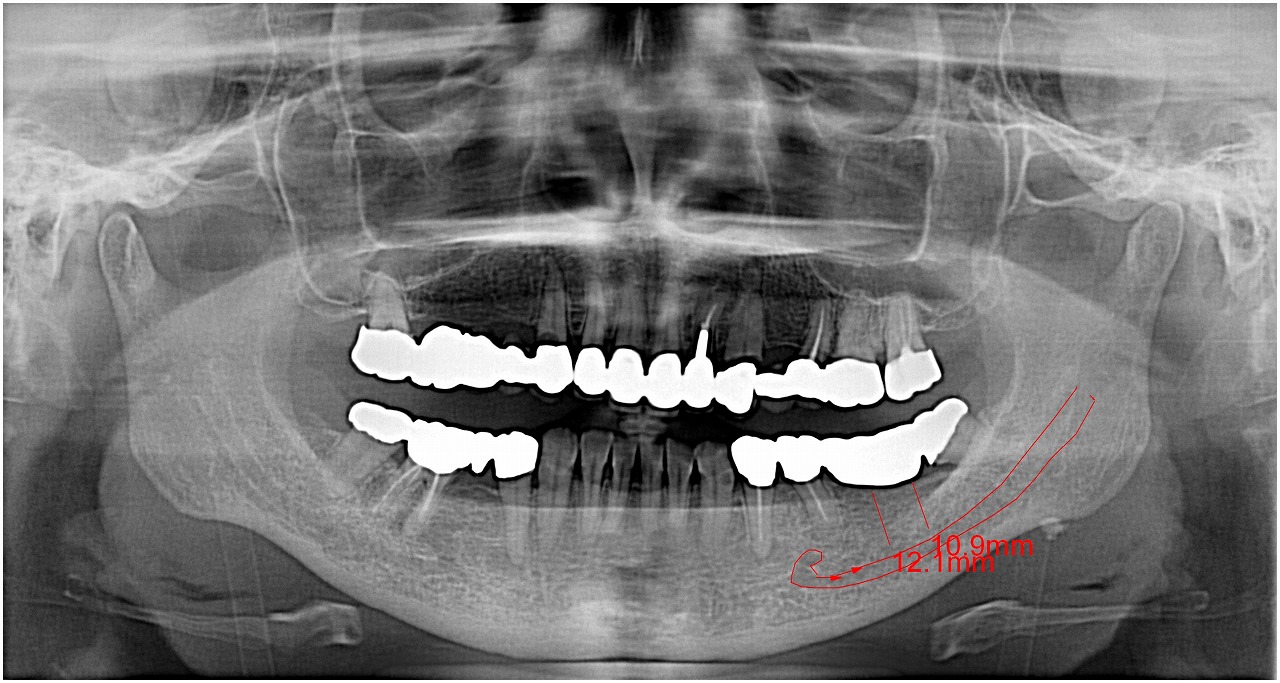

ブログ一覧|広島市安佐南区の歯科医院 ブログ一覧 トップ ブログ一覧 お知らせ スタッフブログ ブログ一覧 お知らせ 2019/08/30 左上4番のインプラントを審美的に本来の歯のように仕上げる お知らせ 2019/08/30 左上4番 乳歯抜歯からのインプラント埋入 審美的に仕上げる お知らせ 2019/08/29 インプラント部の角化歯肉欠如のため歯肉移植 上顎口蓋側歯肉から角化歯肉を採取しての移植 お知らせ 2019/08/29 ジルコニアクラウンフルマウスの作成 お知らせ 2019/08/28 右上インプラントの3連冠ジルコニアクラウンにて作成工程 お知らせ 2019/08/28 8月25日の夜から26日にかけて恩師に会いに博多へ お知らせ 2019/08/27 8月25日、26日と恩師に会いに博多へ お知らせ 2019/08/26 インプラント埋入時の診断 4本をCTからイメージ、時間ともかかわりながらの処置をしていきます << 1 2 3 4 5 … 387 388 389 390 391 … 870 871 872 873 874 >> Web診療予約 初めての方へ 選ばれ続ける理由 院内設備について 歯が痛いしみる一般歯科 歯がぐらぐらする歯周病 健康な歯を保ちたい予防歯科 子供の虫歯予防をしたい小児歯科 銀歯をセラミックに審美歯科 白い歯を目指しませんか?ホワイトニング 矯正専門医がいるので安心矯正歯科 抜けた歯を補いたいインプラント・入れ歯 医院案内 スタッフ紹介 メリィハウス歯科クリニックオフィシャルホームページ ラベンダー歯科クリニックオフィシャルホームページ お知らせ・ブログ ホーム 診療科目 一般歯科 歯周病治療 予防治療 小児歯科 審美治療 ホワイトニング 矯正歯科 入れ歯・インプラント マウスピース矯正 初めての方へ 院長・スタッフ 設備紹介 医院案内・アクセス メニューを閉じる